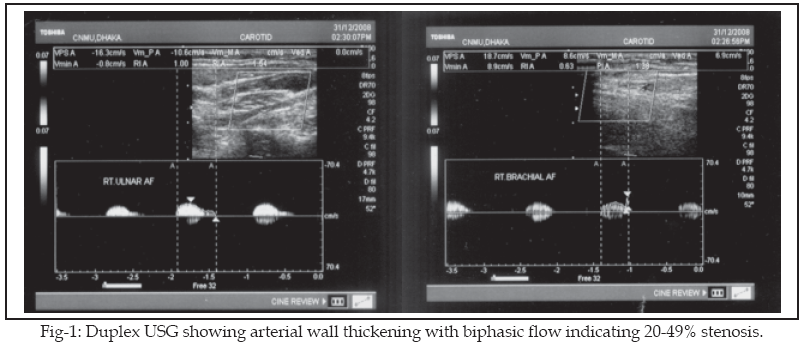

st hour and C reactive protein was 12 mg/L. TPHA was non-reactive and CPK was 45 U/L. Serological study for ANA, c-ANCA and p-ANCA were all negative. Her serum bilirubin, alanine amino transferase, routine microscopic examination of urine, serum creatinine, albumin and lipids profile were normal. Mantoux test was positive and chest X-ray posterior/anterior view was normal.USG of whole abdomen showed normal study and echocardiography reported normal cardiac chambers with normal valvular morphologies. Duplex vascular Ultrasonogram (USG) revealed significant narrowing of both subclavian arteries with descending abdominal aorta (Fig-1).

,s arteritis is a systemic vasculopathy that can progress to cause vital organ ischaemia. Therefore, long term follow up is recommended. We advised our patient for regular follow up. We planned for ESR, CRP and assessment of arterial wall thickness using duplex vascular USG in each time follow up.In the light of this report, we suggest that tuberculosis should be kept in mind during exploration of aetio pathology of Takayasu’s arteritis and we found the use of anti tubercular drug rational during treatment of this disease.